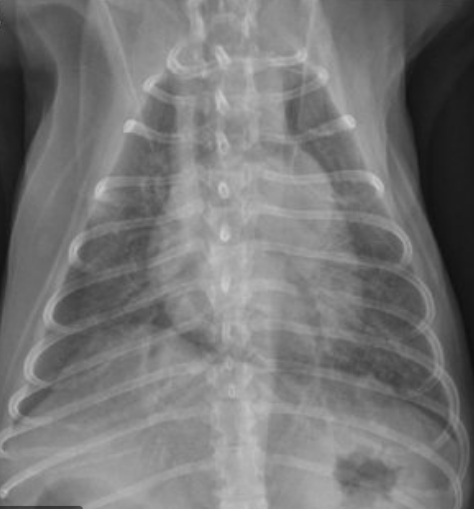

What view is this radiograph an example of?

VD Thorax